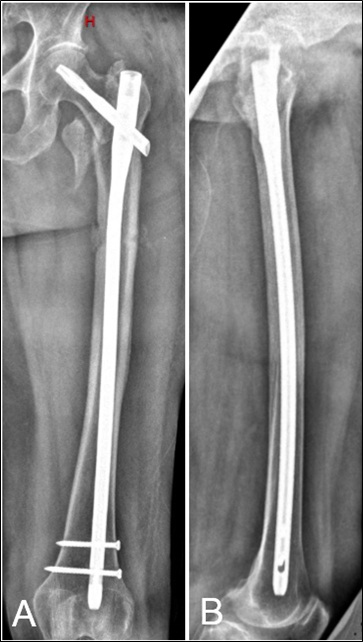

Penetración de la cortical anterolateral en fracturas de fémur proximal tratadas con clavos endomedulares cortos Reporte de dos casos. [Penetration of anterior-lateral cortex in proximal femur fractures treated with short intramedullary nails Report of two cases].

7. Ostrum RF, Levy MS. Penetration of the distal femoral anterior cortex during intramedullary nailing for subtrochanteric fractures: a report of three cases. J Orthop Trauma 2005;19:656-60.